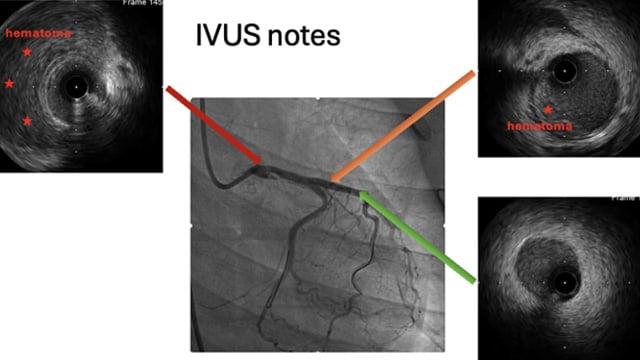

This session explores complex coronary challenges and anatomical anomalies encountered in clinical practice. Topics include management of thrombus showers from unexpected culprits, ultra-low contrast angioplasty in mesenteric ischemia, advanced bifurcation PCI techniques with IVUS guidance, and troubleshooting difficult stent delivery scenarios in calcified lesions and challenging...